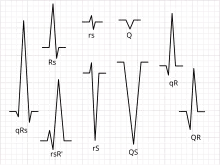

Tous les complexes QRS ne contiennent pas une onde Q, une onde R et une onde S. Par convention, toute combinaison de ces ondes peut être appelée complexe QRS. Cependant, une interprétation correcte des ECG difficiles nécessite un étiquetage exact des différentes ondes. Certains auteurs utilisent des lettres minuscules et majuscules, en fonction de la taille relative de chaque vague. Par exemple, un complexe Rs serait dévié positivement, tandis qu’un complexe rS serait dévié négativement. Si les deux complexes étaient étiquetés RS, il serait impossible d’apprécier cette distinction sans visualiser l’ECG réel.